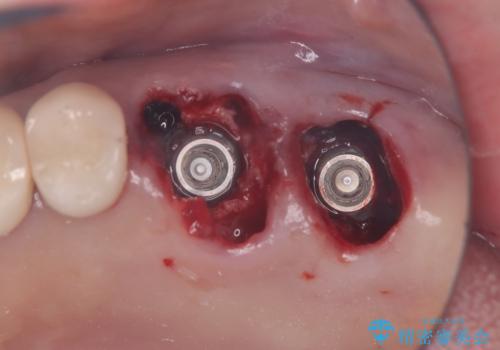

- 金属を外してセラミックを入れたいことを主訴に来院された患者さんです。

セラミックインレーにて修復を行いました。